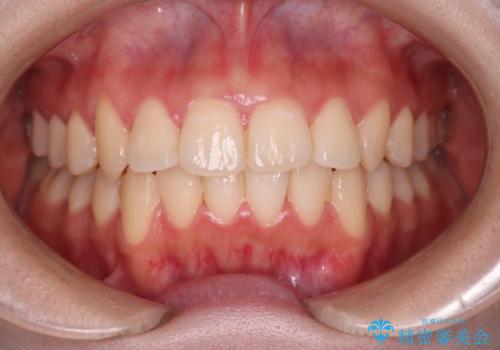

【クリア装置】八重歯とがたつきを綺麗に